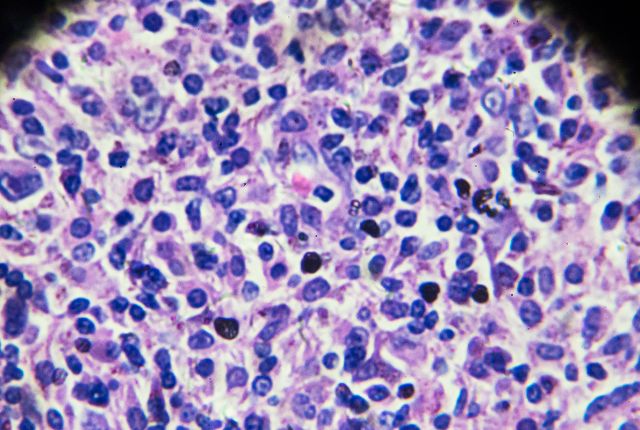

Ceux-ci peuvent mettre en évidence la présence de lymphocytes anormaux et leur diffusion. La biopsie permet de confirmer ou infirmer le diagnostic. Elle peut se dérouler en étant guidée par échographie ou scanner à l'hôpital. Le ganglion peut être retiré en entier (biopsie exérèse). L'analyse anatomopathologique qui suit précise le caractère malin des cellules et le type de lymphome en cours.